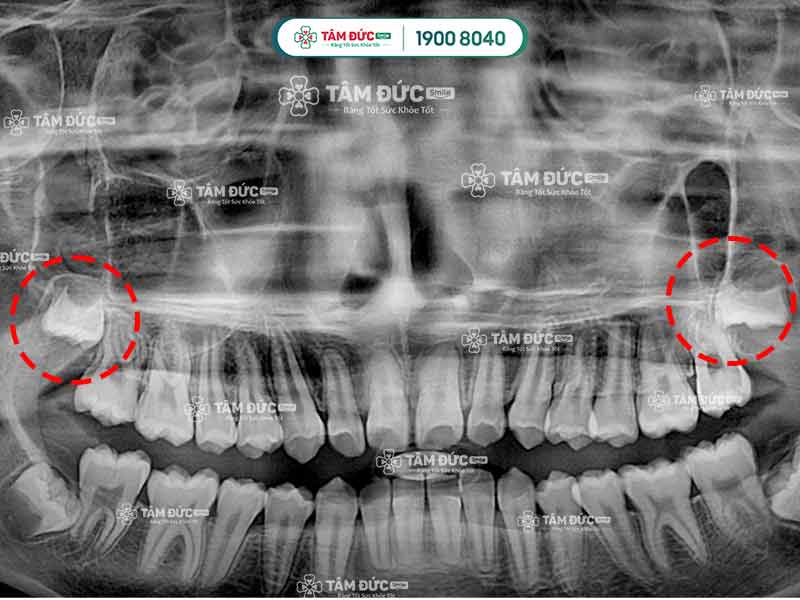

Hai mầm răng khôn đang có dấu hiệu mọc ngầm